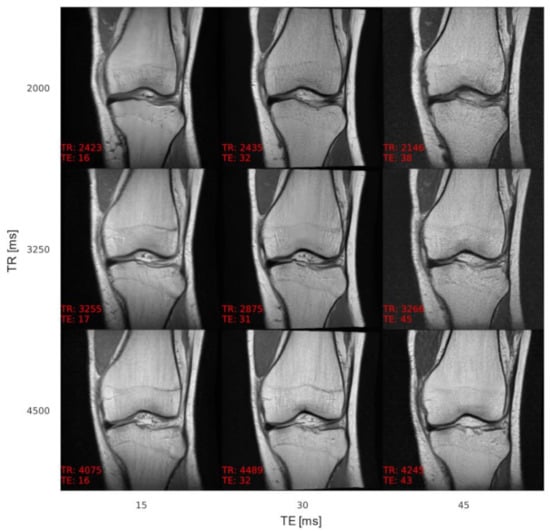

According to the experts, image quality impediments of synthetic MR images were mainly attributed to overly smooth tissue (muscles, fat tissue, and bones) compared to fibrous muscle tissue, granular texture in fat tissue, and fine structures in bones of real MR knee images. Additionally, due to the downsampling of several of the real images to a resolution of 256 × 256 pixels using bilinear interpolation to obtain identical image resolution, the image quality of the real images was described as inferior in certain cases, making it hard for the experts to classify. An example of acquisition parameter interpolation is shown in Figure 3, and additional examples of varying anatomy demonstrating the variability of the generated samples are shown in Figure 4. The effect of TE on the tissue contrast can be seen in signal changes of the muscle tissue (Figure 3). Varying TR results in signal differences in the fluid-cartilage contrast [42] and mainly affects contrast on T1-weighted images [43], which are not available within the dataset (see Section 5. Discussion). Therefore, the signal changes through varying TR are less prominent.

Figure 3. Acquisition parameter interpolation of TR and TE for a single latent vector. A single latent vector was reconstructed with different TR and TE values, showing the capability of the generator to synthesize MR images with adaptable image contrast. The axes describe the intended acquisition parameter values and the values at the bottom left of each image the output of the AC. The images are annotated (in red) with acquisition parameter values as determined by the AC, showing a low overall conditioning error. The contrast adapts properly within images along the axes; however, the anatomy also slightly changes, which is a sign of feature entanglement of the latent vector with the conditions.

Figure 4. Additional examples of synthetic MR images with varying TR and TE to show the variety of the generated image samples. The imaging orientation alternates between sagittal and coronal. The images are annotated (in red) with acquisition parameter values as determined by the AC, showing a low overall conditioning error.